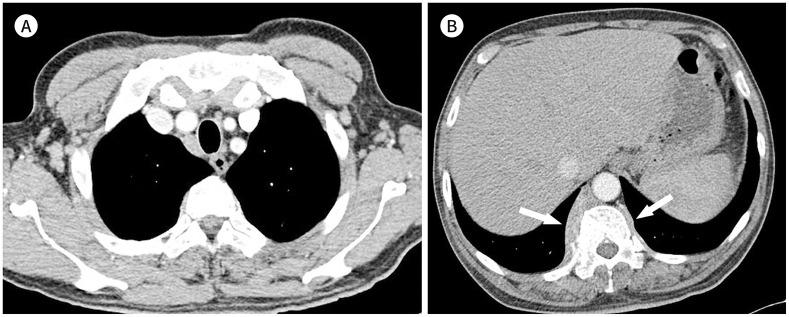

Immunoglobulin G4-related disease (IgG4-RD) is a chronic inflammatory condition involving multiple organs, including the salivary or lacrimal glands, orbit, pancreas, bile duct, liver, kidney, retroperitoneum, aorta, lung, and lymph nodes. It is histologically characterized by tissue infiltration with lymphocytes and IgG4-secreting plasma cells, storiform fibrosis, and obliterative phlebitis. In the thoracic involvement of IgG4-RD, mediastinal lymphadenopathy and perilymphangitic interstitial thickening of the lung are the most common findings. Peribronchovascular and septal thickening and paravertebral band-like soft tissue are characteristic findings of IgG4-RD. Other findings include pulmonary nodules or masses, ground-glass opacity, alveolar interstitial thickening, pleural effusion or thickening, mass in the chest wall or mediastinum, and arteritis involving the aorta and coronary artery. Radiologic differential diagnosis of various malignancies, infections, and inflammatory conditions is needed. In this review, we describe the imaging findings of IgG4-RD and the radiologic differential diagnoses in the thorax.

免疫球蛋白G4相关性疾病(IgG4-RD)是一种累及多个器官的慢性炎症性疾病,这些器官包括唾液腺或泪腺、眼眶、胰腺、胆管、肝脏、肾脏、腹膜后、主动脉、肺和淋巴结。其组织学特征为淋巴细胞和分泌IgG4的浆细胞浸润组织、席纹状纤维化和闭塞性静脉炎。在IgG4-RD累及胸部时,纵隔淋巴结肿大和肺淋巴管周围间质增厚是最常见的表现。支气管血管周围和小叶间隔增厚以及椎旁带状软组织是IgG4-RD的特征性表现。其他表现包括肺结节或肿块、磨玻璃影、肺泡间质增厚、胸腔积液或增厚、胸壁或纵隔肿块以及累及主动脉和冠状动脉的动脉炎。需要对各种恶性肿瘤、感染和炎症性疾病进行影像学鉴别诊断。在本综述中,我们描述了IgG4-RD的影像学表现以及胸部的影像学鉴别诊断。